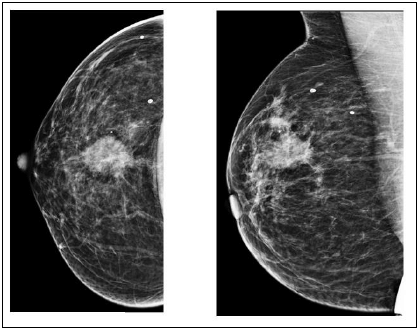

Paciente, 45 anos, encaminhada à mamografia por nódulo palpável em exame físico. Não há exames prévios.

Tal lesão deve ser classificada como BIRADS: